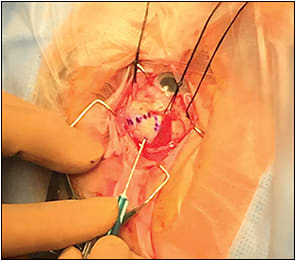

1. Transillumination is necessary for delineation of tumor margins with marking of the sclera using a sterile marking pen or indirect ophthalmoscopy, with a scleral depressor/marker for amelanotic tumors (Figure 1).

Figure 1. Transcleral fine needle aspiration biopsy after tumor transillumination and delineation.